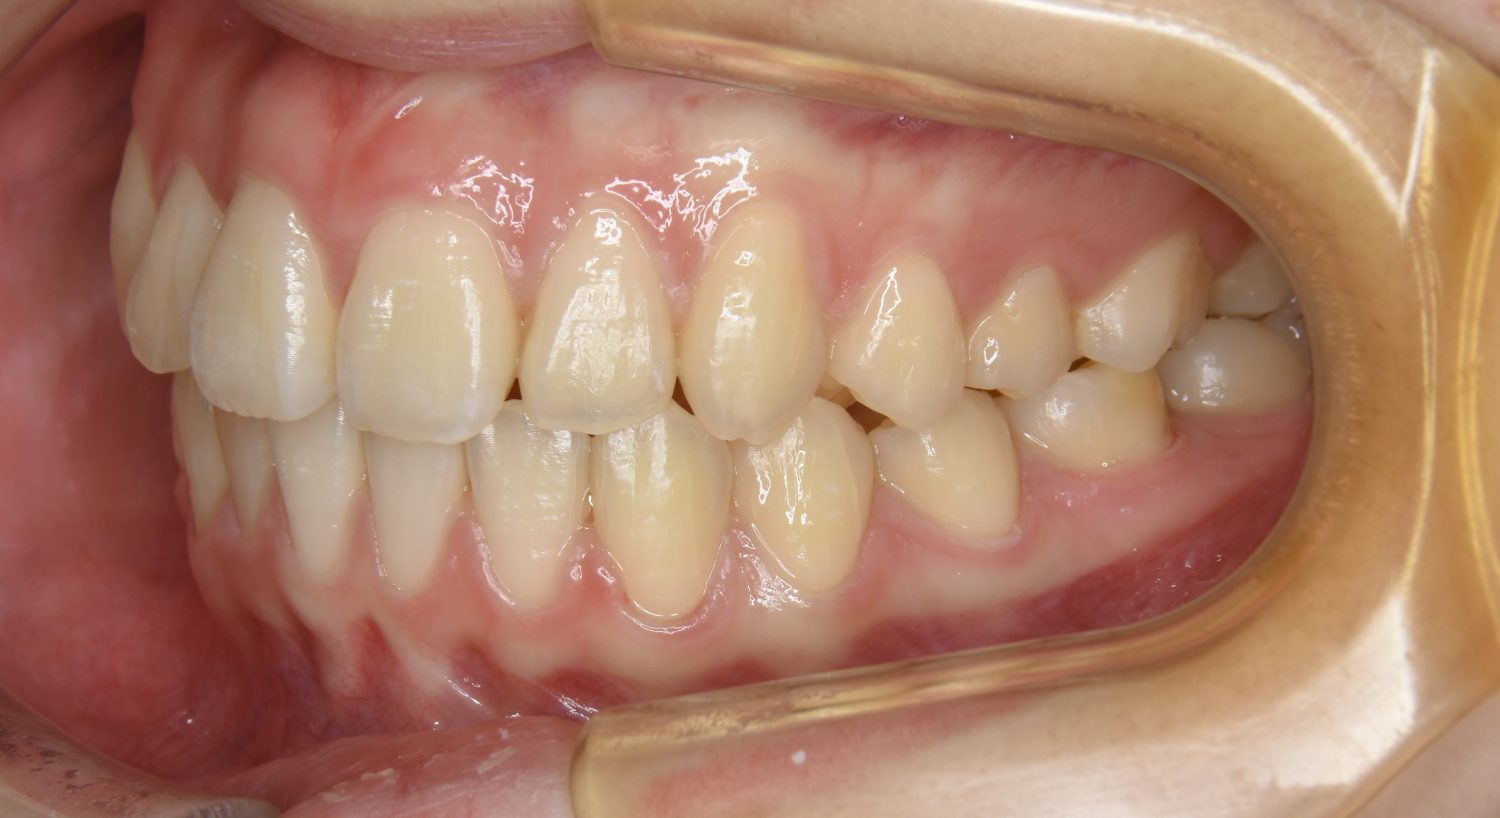

叢生の症例紹介②

Before

After

主訴

歯の凸凹を治したい。

治療内容

アライナー(インビザライン)にて非抜歯で治療を行いました。

治療費

1,150,000 円(税込)

治療期間

26ヶ月

通院回数

14回

想定されたリスク

※歯根吸収、歯肉退縮、歯髄壊死、顎関節症状

※アライナー(インビザライン)は日本の薬機法未承認の矯正装置であり、医薬品副作用被害救済制度の対象外となる場合があります。

丸山和宏先生

ピーススマイル矯正歯科

上下前歯部に叢生(凸凹)が認められる状態でした。歯列の遠心移動を行うことで機能面および審美面が改善されました。